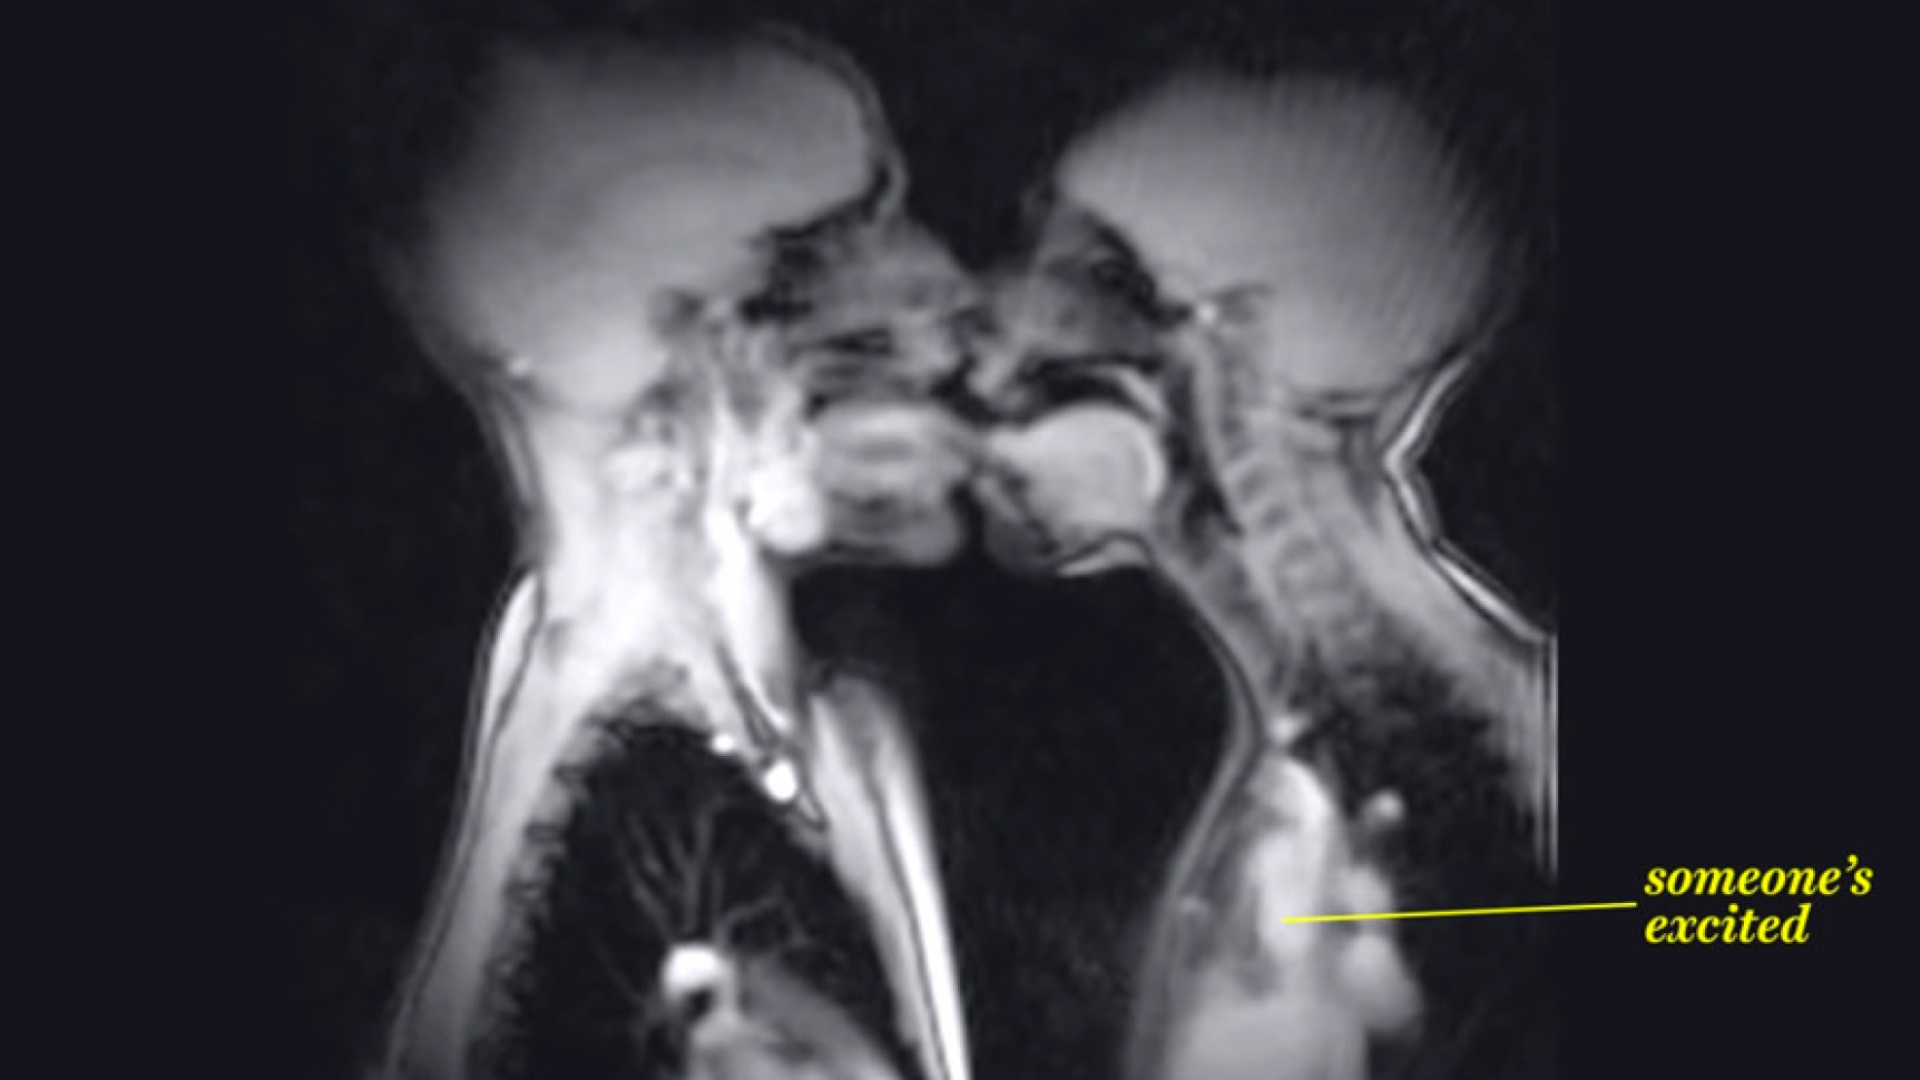

Otsikkokuvassamme on kuvattuna suutelevat ihmiset MRI-laitteella, eli kuvannettuna ydinmagneettiseen resonanssiin perustuvalla mageettikuvauslaitteella. Normaalisti sairaanhoidossa käytettävä laite on erinomainen paitsi siksi, että siinä ei tutkittavaan potilaaseen ei jouduta kohdistamaan röntgensäteilyä, vaan hänen sisuskalunsa saadaan näkyviin veden sisältämien vety-ytimien magneettikentässä lähettämää radiosignaalia havaitsemalla. Ja verrattuna normaaliin röntgenkuvaan on MRI erinomainen myös siksi, että sen avulla pystytään kuvantamaan videoita – siis ihmiskehoa toiminnassa.

Vox.com -nettisivu on tehnyt jännittävän koosteen (joka on myös alla) MRI-kuvista, joissa taitsi suudellaan, niin myös näytetään muita elintoimintoja. On oikeastaan häkellyttävää nähdä mitä sisällämme tapahtuu ja miten elimemme toimivat.